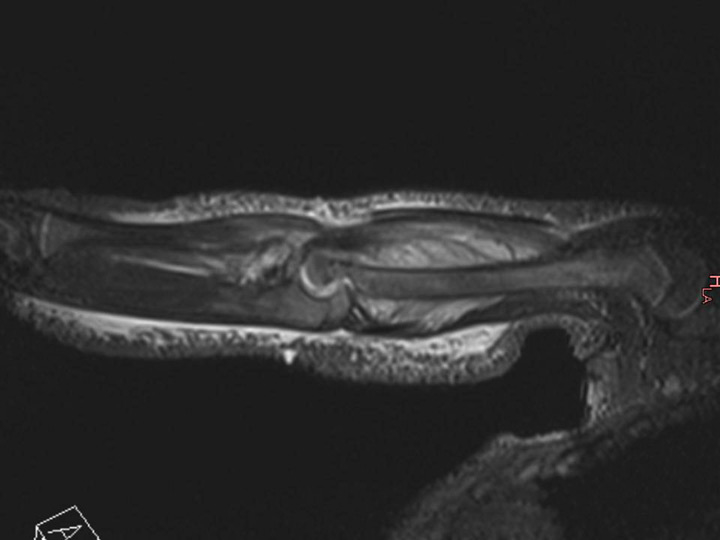

Figure 3

Magnetic resonance imaging (MRI) of the distal femur of a 17-month-old boy, which showed a normal appearance on plain radiographs. MRI demonstrated a lytic lesion of the distal femoral epiphysis with an important abscess of the soft surrounding tissues. Specific cultures confirmed tuberculosis.

PSAHO can be divided into two main clinical forms according to the age of the child and its bacteriological aetiology. The first form, the infantile form, affects children aged between 6 months to 4 years. Approximately 90% of all PSAHO affect patients in this age group with K. kingae as the main observed microorganism (personal data to be published). In these young children, the clinical course of PSAHO is most likely explained by the natural low virulence of K. kingae. K. kingae osteoarticular infection is characterised by a mild-to-moderate clinical and biologic inflammatory response to infection with few (if any) criteria evocative of OAI. Many children in this age group are usually recognised late as having an osteoarticular infection, and an accurate diagnosis is generally delayed until after a bony lytic lesion has occurred (fig. 3). The second form, the juvenile form, affects children older than 4 years and S. aureus appears as the main bacteriological aetiology. In this situation, PSAHO is most likely the result of an increased host resistance and it can be hypothesised that the children who develop this resistance against S. aureus become able to contain the bone infection. Indeed, colonisation is recognised to be more frequent among children [43]. Remarkably, 20% of individuals are persistently colonised by S. aureus in the nares and 30% are transiently colonised [44]. Although colonisation predisposes an individual to S. aureus infection, colonised individuals may have less severe S. aureus disease compared with non-colonised individuals [45]. This raises the question as to whether colonisation could induce low level, adaptive immunity and subsequent milder infections [44].